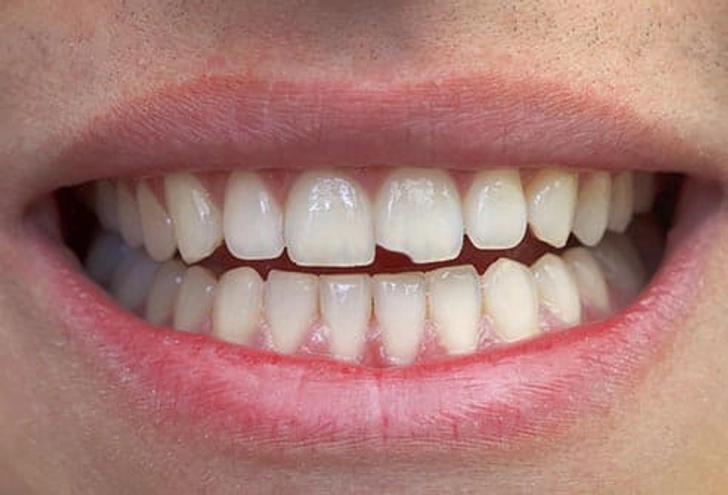

۶. ترک خوردگی دندان

ترک ممکن است در اثر بازی ورزشی بدون محافظ، یا حتی جویدن ایجاد شود.

- در بیشتر موارد روکش توصیه میشود تا از گسترش ترک جلوگیری شود.

- اگر دندان به گرما و سرما حساس باشد، مشکل پیچیدهتر است و ممکن است نیاز به عصب کشی و روکش باشد.

- ترک عمیقتر معمولاً منجر به کشیدن دندان میشود.

- پرکردگیهای بزرگ احتمال ترک را افزایش میدهند.